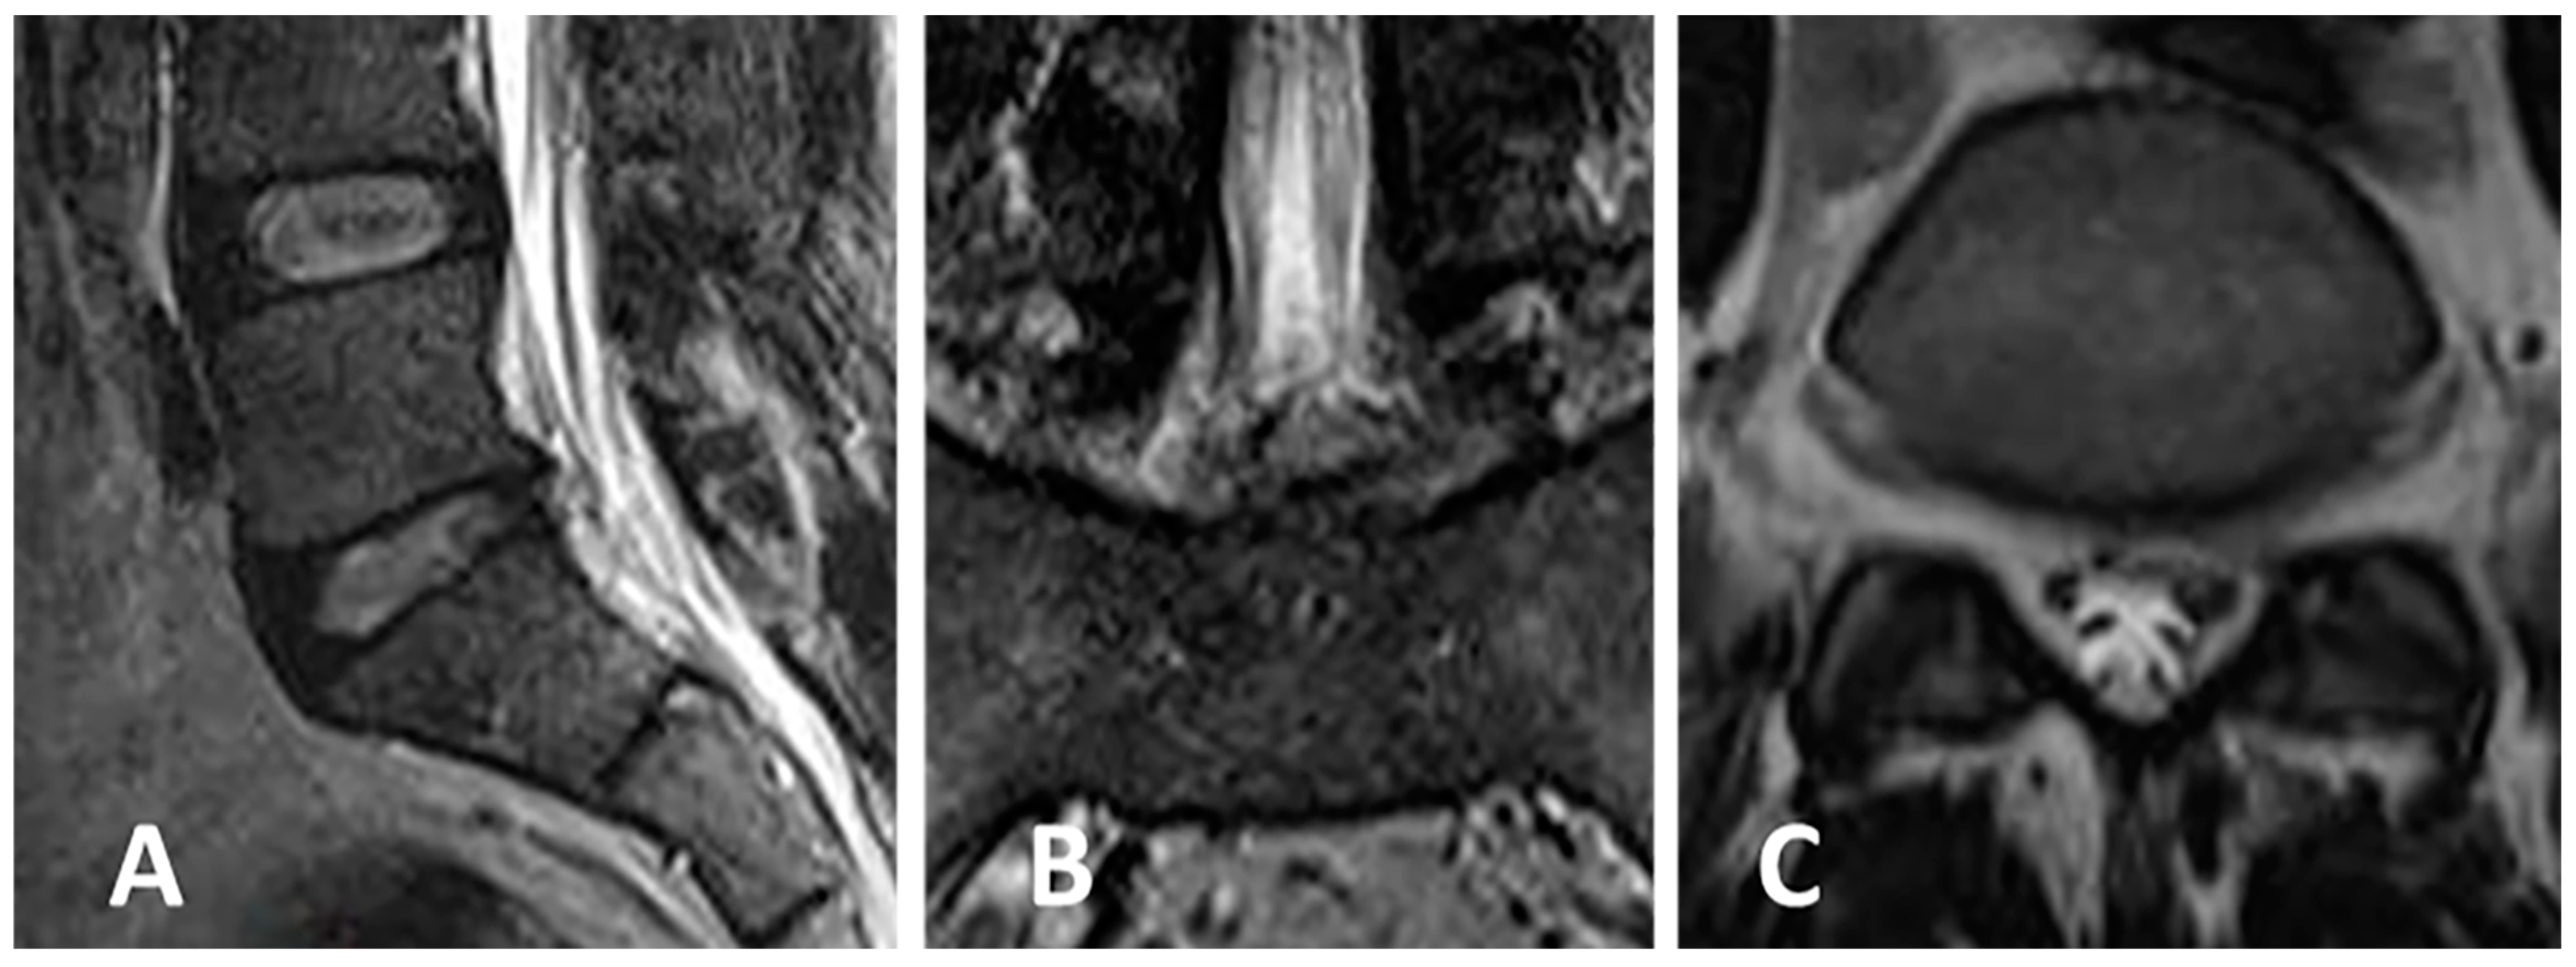

3.4. Clinical Case 2